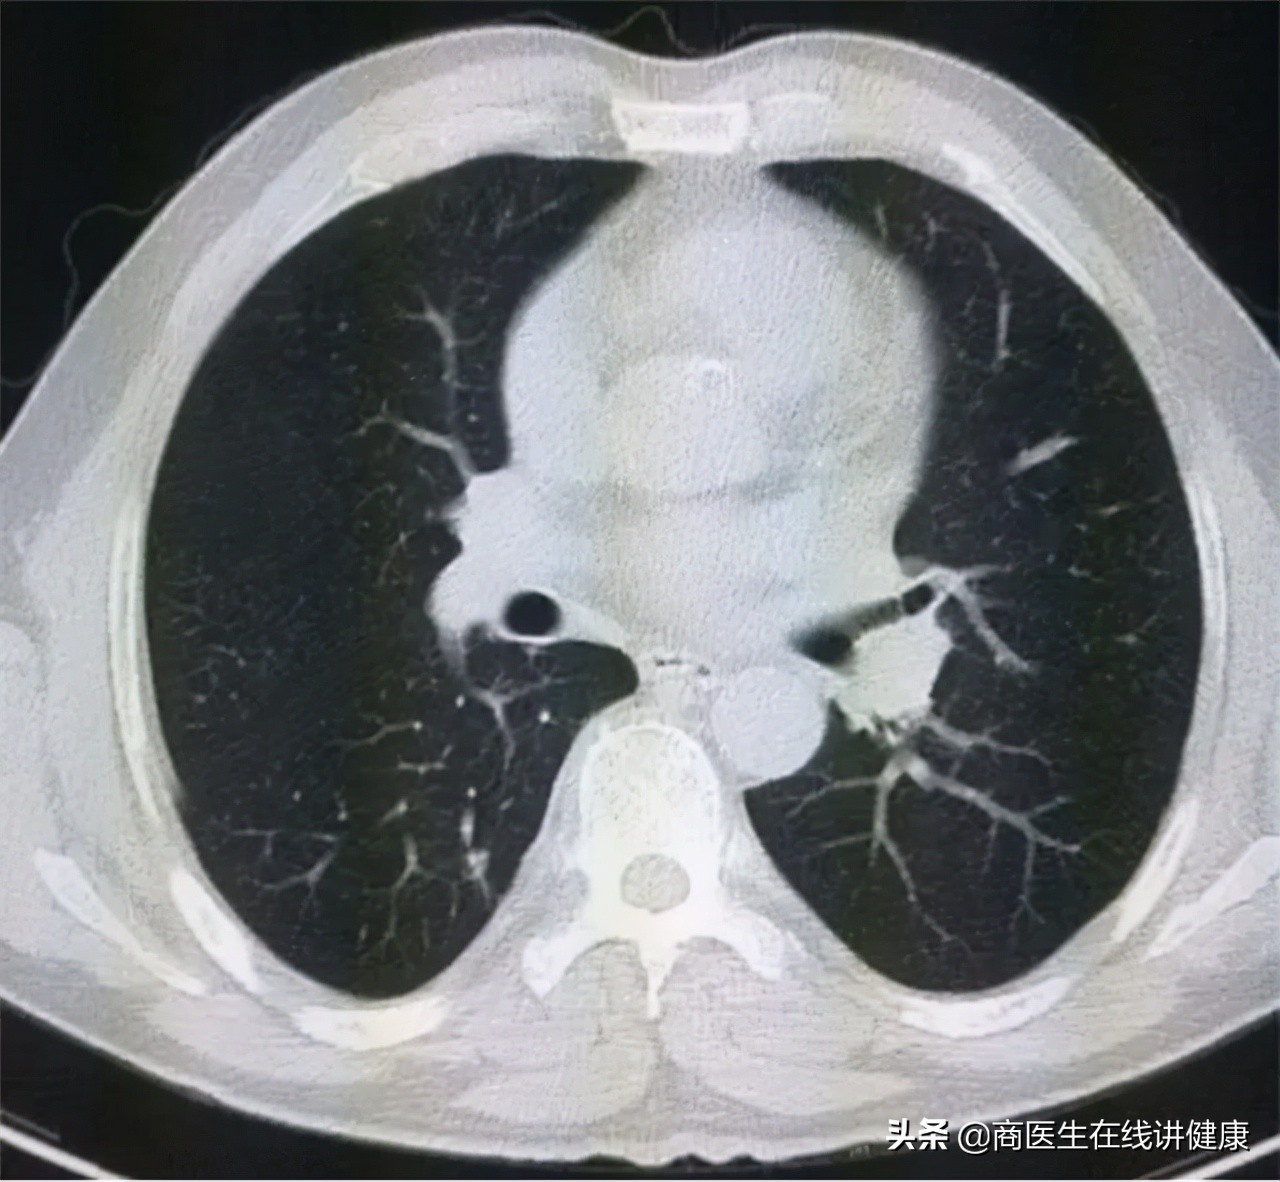

经过对患者叶女士询问后,我们首先推荐患者去做胸部CT。拿到CT结果后,发现患者果然在 双肺多处均有结节状影像,存在多发性结节的情况。从CT上看,结节的大小和实性均不一。但从大小上看,都属于微小结节,且性质上也均属于毛玻璃状。

连续入院治疗十天后,患者叶女士咳嗽及咳痰等症状已明显缓解 ,随后再次做了肺部CT复查,CT检查结果显示,多个肺部结节已经通过治疗后消失,仅有右肺下叶处一个结节仍在影像结果中有显示,但对比入院的CT结果来看,此结节的影像也有所变淡,但大小并无明显变化。